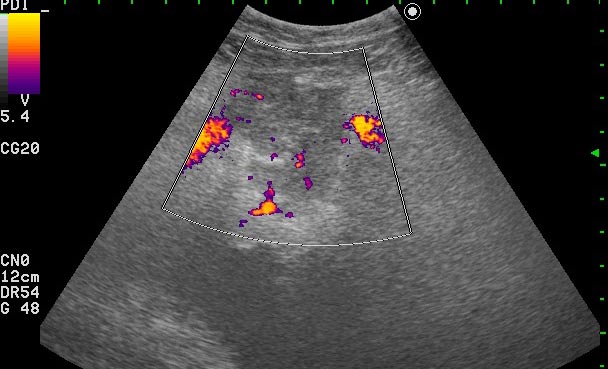

УЗИ - Воспаление урахуса

Женщина 42 лет с болями внизу живота, дизурическими явлениями, повышением температуры.

Сонограммы мочевого пузыря

Похоже на опухоль, но по анамнезу я больше склоняюсь к воспалению урахуса!

Согласна с первым постом-возможно нагноение урахуса(и клиника подходит)

Пациентке была выполнена биопсия образования, назначена антибактериальная и противовоспалительная терапия.

Клиническое выздоровление через 2 недели. Сонограммы мочевого пузыря через 6 недель: